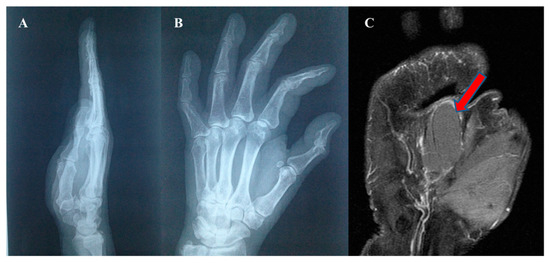

| 2 | Glomus Tumor |

| Difficult to examine due to the pain produced by simple touch. Small, well-defined, hypoechoic tumor. Echo-doppler—intratumoral vascularization | - |

| 5 | Inclusion Epidermal Cyst |

| Well-defined tumor mass with a relatively thick wall and homogeneous content | Well-defined cystic tumor formation, with hypersignal in T2 and hyposignal in T1 |